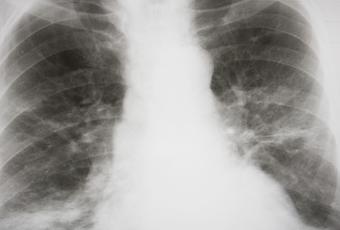

Ante estos síntomas, el médico determinará con radiografía que se trata de una neumonía y no de otra infección respiratoria, como una bronquitis. Los objetivos del tratamiento –los antibióticos no sirven para este tipo de neumonía– son mejorar la respiración con el uso de humidificadores y oxígeno, y prevenir la deshidratación. Por eso se recomienda ingerir abundantes líquidos, que ayudarán a expulsar la flema y las secreciones.